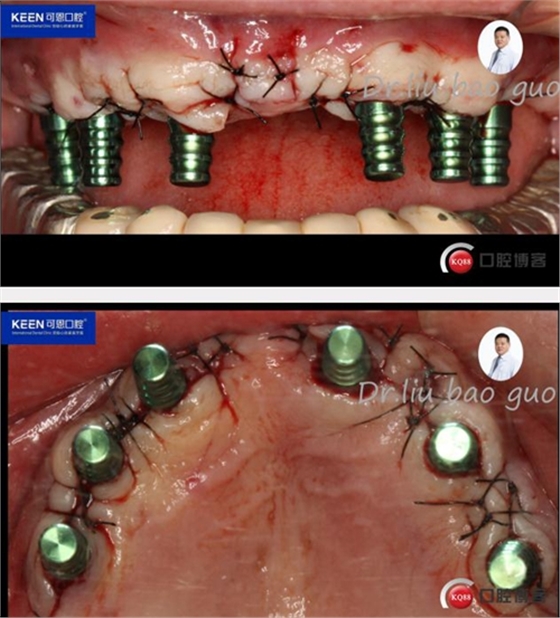

手術(shù)過(guò)程

(因設(shè)備限制,未能實(shí)現(xiàn)手術(shù)全程數(shù)字化導(dǎo)板,僅在手術(shù)之前導(dǎo)板定位)